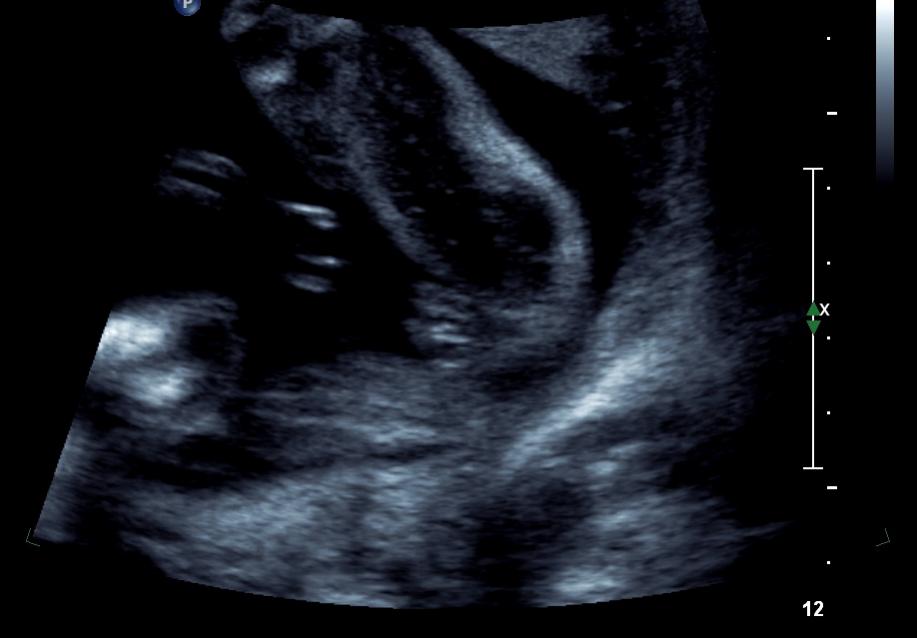

Posted my nub shots a while ago and got all girl guesses. Had a gender scan at 22 weeks and tech said girl too...Is this all GIRL!!!!!!Attachment 746